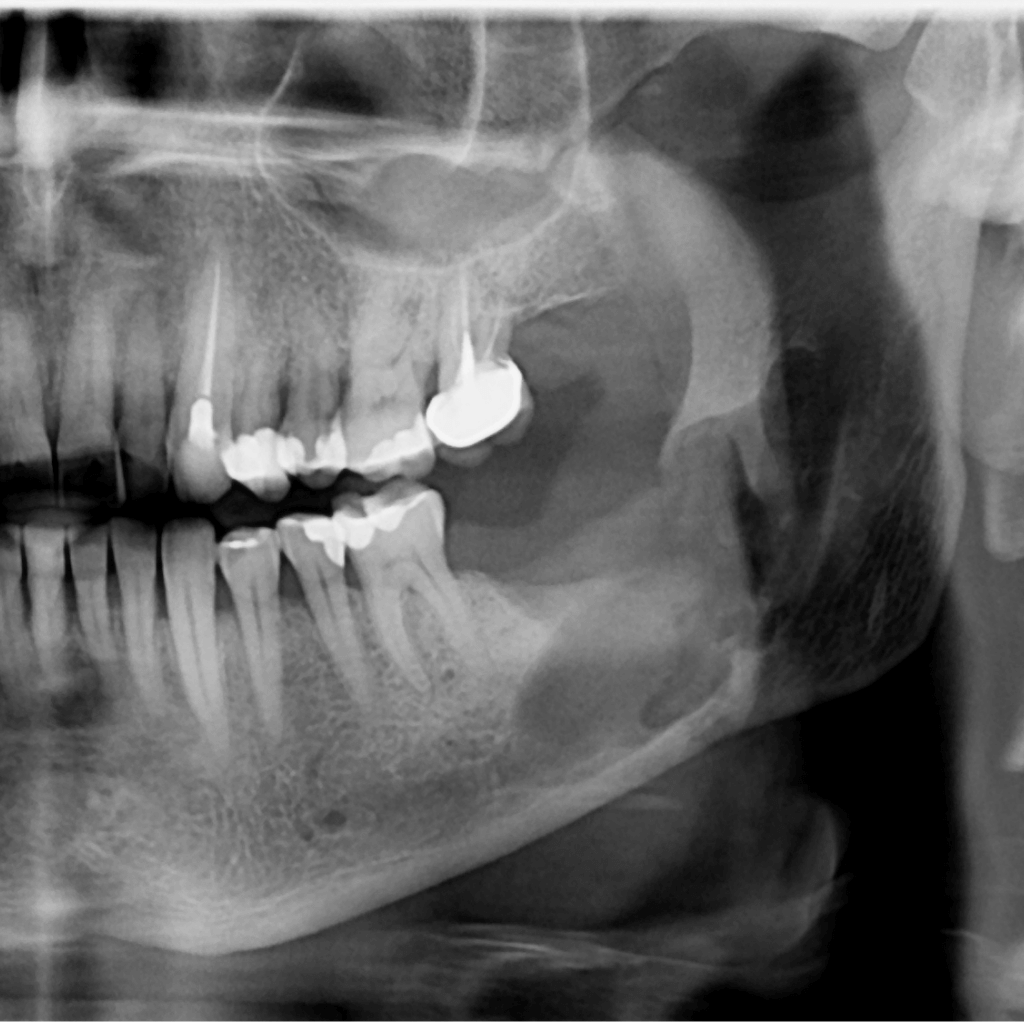

Денталните импланти са съвременно решение за възстановяване на липсващи зъби, което позволява стабилна функция и естествено усещане. Те заместват корена на липсващия зъб и служат като основа за коронка, мост или по-голяма конструкция. Имплантологичното лечение цели не само възстановяване на дъвкателната функция, но и запазване на костта и дългосрочна стабилност на захапката.